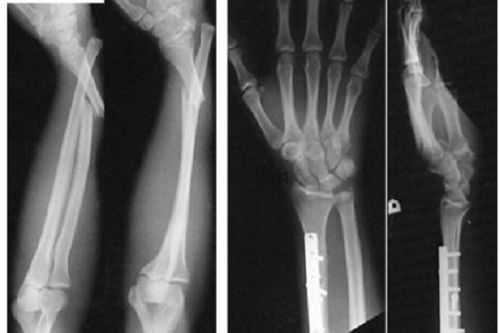

Chụp X-quang là một công cụ chẩn đoán hữu hiệu trong việc đánh giá tình trạng gãy xương đầu dưới xương quay. Kết quả hình ảnh cung cấp thông tin chi tiết về kiểu gãy xương và các tổn thương liên quan khác, bao gồm:

• Gãy ngoài khớp;

• Gãy di lệch theo các hướng khác nhau như phía trên hoặc phía sau, ra ngoài;

• Gãy kèm theo đầu dưới xương trụ, mỏm trâm trụ, xương thuyền;

• Trật khớp quay-trụ dưới;

• Gãy bong sụn ở đầu dưới xương quay (đặc biệt phổ biến ở trẻ em)

Kết quả chụp X-quang, tiền sử chấn thương và những biểu hiện lâm sàng như đau, sưng nề cổ bàn tay, biến dạng lệch khớp cổ tay, suy giảm hoặc mất chức năng vận động cổ tay là những căn cứ quan trọng để xác định gãy đầu dưới xương quay.

Chụp X-quang là một công cụ chẩn đoán hữu hiệu trong việc đánh giá tình trạng gãy xương đầu dưới xương quay.